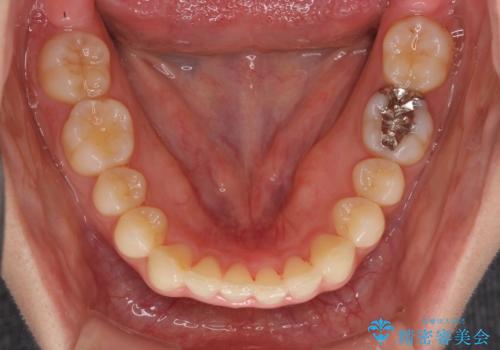

インビザラインによるディープバイトの改善

- 口元の前突感と深い咬み合わせ(ディープバイト)を気にして来院された患者様です。

インビザラインによる上下歯列の遠心移動(後方移動)と、それに伴う近心傾斜(前方傾斜)の改善により、口元の突出感とディープバイトを改善することとしました。

前歯のデコボコを最も気にしていましたが、咬み合わせが深く歯ぎしりが自由にできない点を指摘すると、常に食いしばってしまうことも悩みであることが分かりました。

咬合状態が大きく変化したため、治療後半では咬み合わせの位置が定まらなくなりました。上下の前歯に後戻り防止用のワイヤーを装着し、奥歯の咬合をフリーにしたことで1ヶ月ほどで咬み合わせが定まりました。